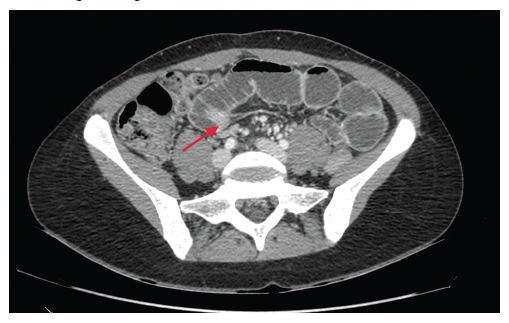

Paciente de sexo femenino de 30 años, con el único antecedente quirúrgico de haber sido operada el año 2002 por un cuadro de peritonitis apendicular por vía abierta. La paciente consulta por sus propios medios en la unidad de urgencia de nuestro centro por un cuadro de 72 horas de evolución, caracterizado por distensión abdominal progresiva, dolor abdominal difuso tipo cólico, vómitos y ausencia de eliminación de gases y deposiciones. Al examen físico se evidencia la cicatriz de la laparotomía mediana supra e infraumbilical (LMSIU), dolor a la palpación, sin irritación peritoneal y ruidos hidroaéreos disminuidos. Se solicita una tomografía axial computarizada (TAC) de abdomen y pelvis con contraste. La TAC mostró dilatación patológica de asas de intestino delgado, con un cambio de calibre hacia el hipogastrio, con colapso de asas a distal y sin signos de sufrimiento intestinal (Figura 2).